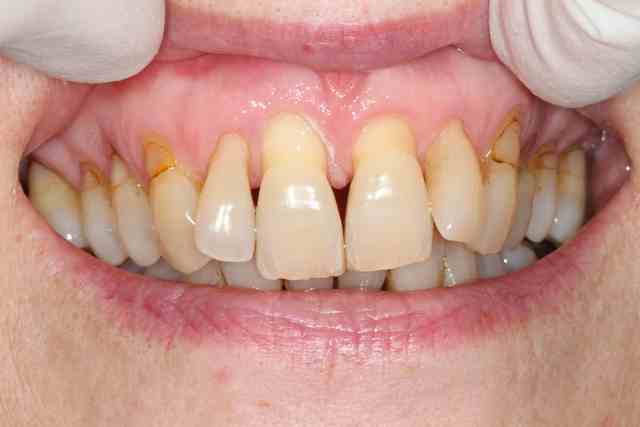

j'ai un cas similaire qui cicatrise et puisque que l'on parlait de recouvrement gingival, voilà un cas où j'espère un résultat sympa... en tout cas c'est prometteur

1 et 2 pré op

3 6 semaines après extraction

4,5,6 intervention avec pilier et barre titane

7 3 semaines post chir à la dépose des points